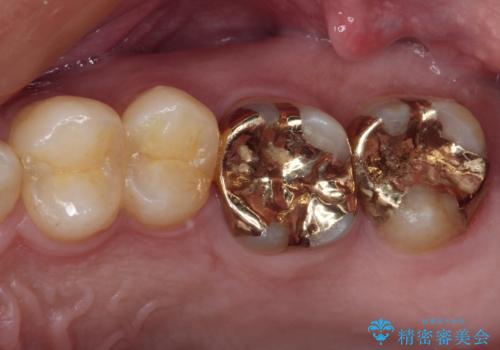

捻れた前歯と銀歯のブリッジを治したい ワイヤー矯正とオールセラミックブリッジ